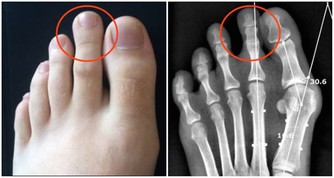

關節炎是一種影響所有年齡段人群的常見病症,它的症狀包括運動受限制、關節疼痛、關節出現炎症,以及受影響區域的皮膚紅腫發燙。